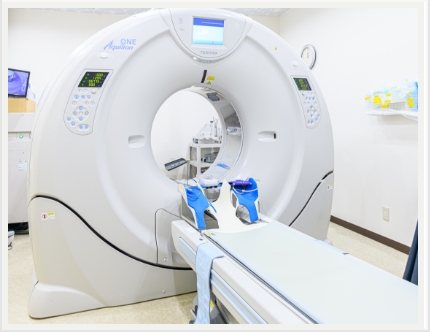

装置・機器紹介

64列CT:Aquilion64(64列検出器を有するX線CT装置)

320列CT:Aquilion ONE/Global Standard Edition(320列検出器を有するX線CT装置)

※画像は64列CTのものです